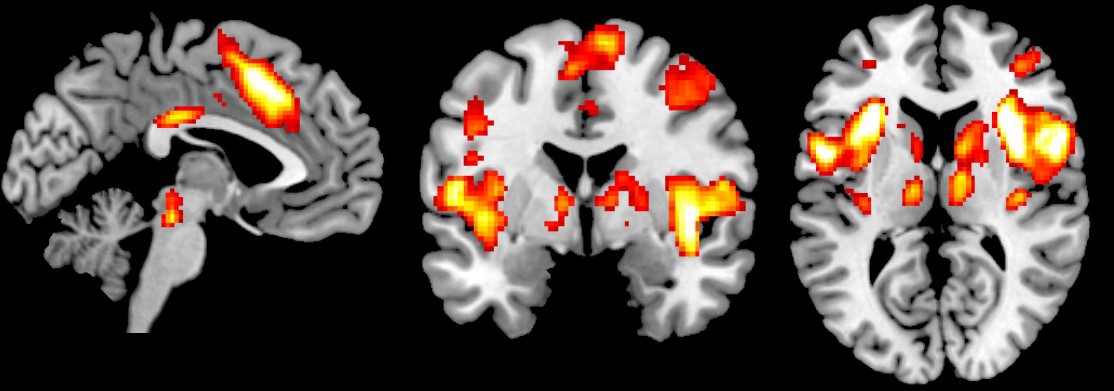

Studies of the brain using MRI scans have given us a good deal of information about acute pain – the day-to-day type that comes and goes – and the areas of the brain that are involved in it, such as the somatosensory cortex, insula, anterior cingulate cortex, some brain stem areas and the thalamus, he said.

MRI scan showing the areas of the brain involved in sensing intense pain. Average of 42 subjects experiencing intense (~7-10) pain. (Image provided)